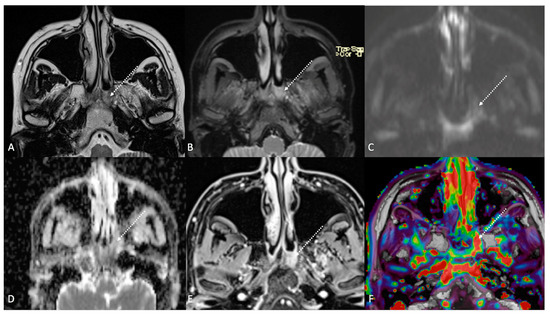

Figure 3.

Post-treatment magnetic resonance imaging (MRI) of a 63-year-old female patient with human-papillomavirus-positive carcinoma of the right palatine tonsil with ipsilateral lymph node metastasis (T2N1) recently treated (3 months before) with chemoradiotherapy (CRT). Post-CRT MRI showed linear fibrotic tissues in the right palatine tonsil (white striped arrows) with hypointense signal intensity on T2-weighted (A), T2-weighted fat-saturated, (B) and diffusion-weighted b800 images (C), and intermediate apparent diffusion coefficient values (1.44 × 10−3 mm2/s) (D). After gadolinium contrast agent injection, post-CRT fibrotic tissue showed no submucosal enhancement (E) and low K(trans) value (48.36 × 10−3 mm2/s) on dynamic contrast enhancement-perfusion weighted imaging (F). Ratio between K(trans) values of the primitive tumor and residual tissue after CRT, standardized with respect to K(trans) value of the ipsilateral trapezius (K(trans)post/pre/muscle), was 0.307. These findings are typical of post-CRT scar tissue.